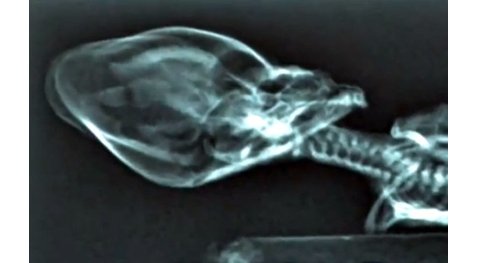

Ο σκελετός των 15 εκατοστών, ο οποίος ανακαλύφθηκε πριν από δέκα χρόνια στην έρημο Ατακάμα της Χιλής, και όλοι πίστεψαν ότι επρόκειτο για τον ανθρωπόμορφο εξωγήινο με το παρατσούκλι, Ata, μας απογοήτευσε.

Τελικά οι επιστήμονες του πανεπιστημίου του Στάνφορντ απέδειξαν ότι ήταν άνθρακας ο θησαυρός. Κι αυτό συνέβη ενώ απομένουν λίγες ημέρες για την προβολή του ντοκιμαντέρ «Sirius», το οποίο περίμεναν πώς και πώς οι φίλοι των ΑΤΙΑ για να μάθουν για την καταγωγή του Ata. Ύστερα από πολύχρονες έρευνες και εξειδικευμένα τεστ DNA οι επιστήμονες του Πανεπιστημίου του Στράτφορντ κατέληξαν στο συμπέρασμα ότι πρόκειται για μεταλλαγμένο άνθρωπο. Οι ειδικοί τονίζουν ότι ο σκελετός προσομοιάζει έντονα σ' αυτό που μέχρι σήμερα πιστεύαμε ότι είναι η μορφή των εξωγήινων. «Μπορώ να σας πω με βεβαιότητα ότι δεν είναι πίθηκος. Είναι ένα ανθρωποειδές. Έζησε το πολύ για έξι με οκτώ χρόνια. Ανέπνεε, έτρωγε και είχε και μεταβολισμό. Άγνωστο παραμένει, βέβαια, το μέγεθός του όταν γεννήθηκε», δήλωσε ο επικεφαλής του τμήματος κυτταρικής βιολογίας, Γκάρι Νόλαν.